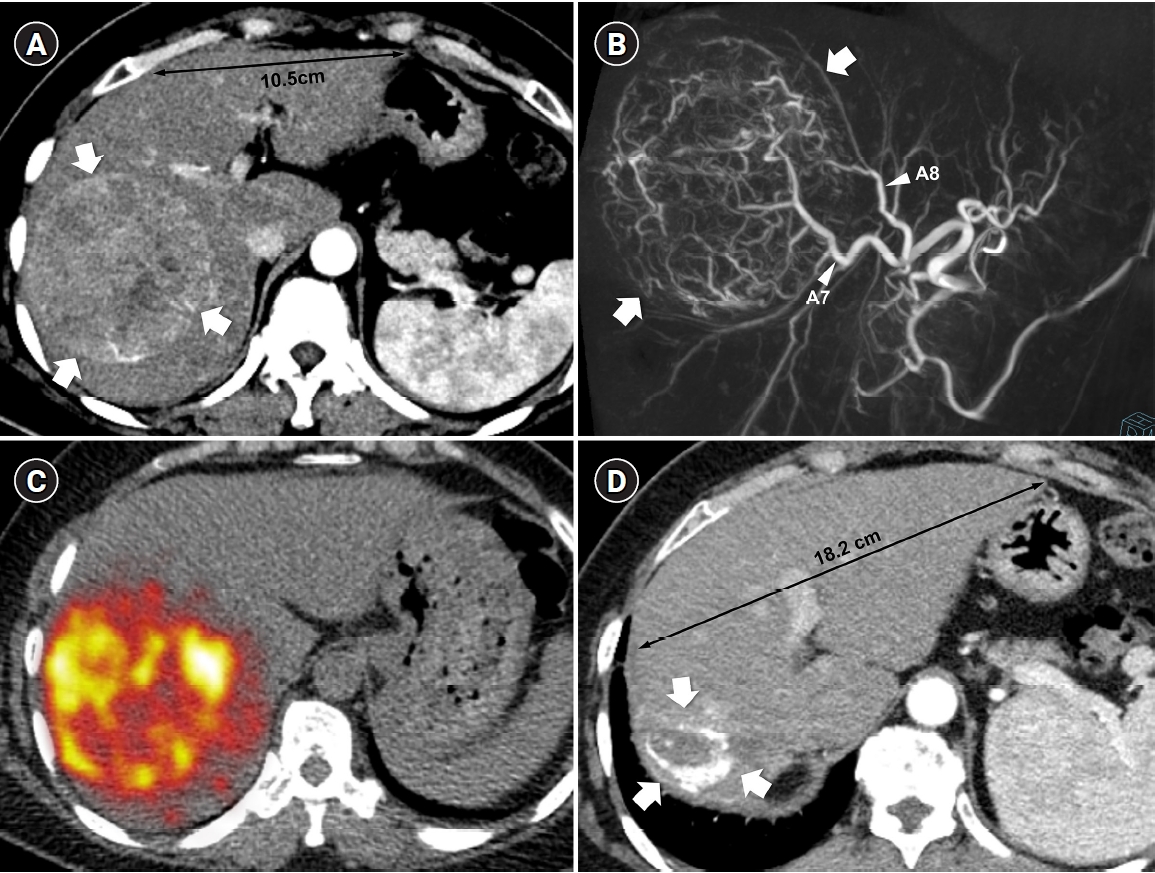

Radiation subsegmentectomy in an 86-year-old man with a single nodular hepatocellular carcinoma. (A) Liver magnetic resonance imaging shows a 2.2-cm hypervascular tumor (arrow) with exophytic growth in segment 6. (B) Hepatic arteriography shows a hypervascular tumor (arrows), and the microcatheter was advanced into a subsegmental branch of A6 (right side image). A total activity of 0.35 GBq of glass microspheres was infused. (C) Post-treatment Y-90 positron emission tomography shows intense uptake at the tumor (arrow), confirming a perfused liver dose of 508.7 Gy and a tumor dose of 1,794.7 Gy. Voxel-based dosimetry showed a D95 of 625 Gy and a V200 of 100% (D95: the minimum dose delivered to 95% of the target volume, V200: the percentage of target volume receiving ≥200 Gy). (D) Twenty-month follow-up computed tomography shows complete response with dystrophic calcification (arrow).

Fig. 1. Radiation subsegmentectomy in an 86-year-old man with a single nodular hepatocellular carcinoma. (A) Liver magnetic resonance imaging shows a 2.2-cm hypervascular tumor (arrow) with exophytic growth in segment 6. (B) Hepatic arteriography shows a hypervascular tumor (arrows), and the microcatheter was advanced into a subsegmental branch of A6 (right side image). A total activity of 0.35 GBq of glass microspheres was infused. (C) Post-treatment Y-90 positron emission tomography shows intense uptake at the tumor (arrow), confirming a perfused liver dose of 508.7 Gy and a tumor dose of 1,794.7 Gy. Voxel-based dosimetry showed a D95 of 625 Gy and a V200 of 100% (D95: the minimum dose delivered to 95% of the target volume, V200: the percentage of target volume receiving ≥200 Gy). (D) Twenty-month follow-up computed tomography shows complete response with dystrophic calcification (arrow).